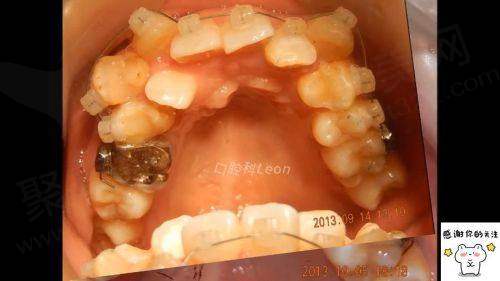

此外,刘医生还擅长处理各种复杂的正畸问题,如牙列拥挤、牙列稀疏、龅牙、地包天等。她凭借自己的专精知识和丰富的临床经验,能够正确地诊断问题,并制定出科学有效的治疗方案。她的治疗成效显著,让许多患者重拾自信的笑容。

患者C:我有牙列拥挤的问题,一直想矫正但又担心成效不好。找到刘姗姗医生后,她根据我的情况制定了个性化的矫正方案。在矫正过程中,她定期复诊,及时调整方案。现在我的牙齿已经有了明显的改善,变得整齐了许多。刘医生的专精和负责让我对矫正充满了信心,我相信更终一定能达到理想的成效。